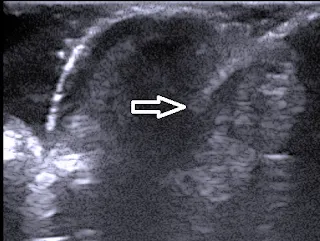

| Imagen ecográfica de un angioma en fase de crecimiento |